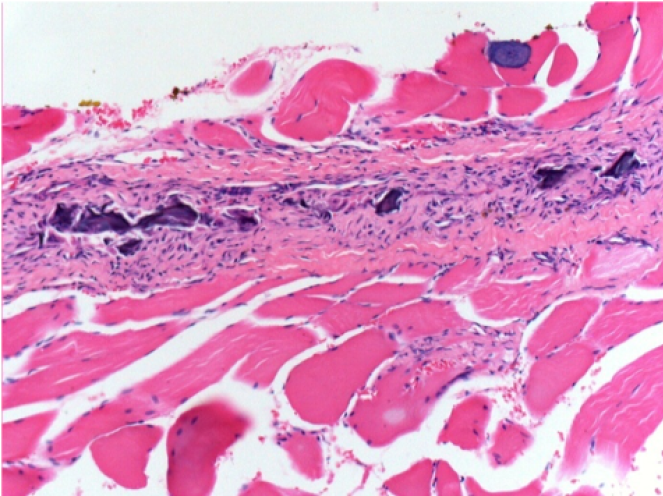

حقن إندوبيل في الأنسجة تحت الجلد

0.5 مل (5 × 0.1 مل) حقن Endopeel SC في المنطقة تحت الجلد اليمنى.

L:200x-Control-SC

R-D10-SC-200X

R-D30-SC-200X

R-D90-SC-200X

R-D210-SC-200X

R-D210-SC-400X

يستحث Endopeel انحلال عضلي عضلي قابل للانعكاس الانتقائي ورد فعل التهابي في فترة شهر واحد تقريبًا

- التغييرات العضلية قابلة للانعكاس في مجملها بالكامل تقريبًا

- العضلة هي أفضل مكان لحقن Endopeel بسبب فعاليتها وتحكمها ومدة عملها

- لم يتم العثور على أي نخر أو خراج في جميع أنحاء الدراسة.